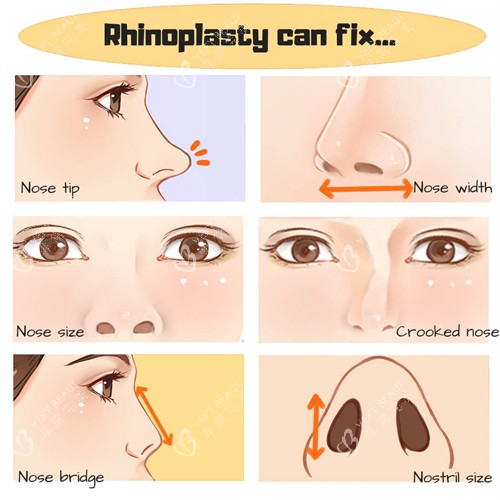

首先,医生的特色资质是基础,一定要查看医生的执业证书和相关的特色认证,确保他是合法合规的。其次,丰富的临床经验至关重要,经验充足的医生在面对各种复杂情况时能更从容地处理。我会查看医生的病例数量和质量,了解他擅长的鼻修复类型。

再者,医生的审美也很关键,要和自己的审美观念相契合,这样才能达到自己想要的结果。然后,医生的沟通能力也不容忽视,一个好的医生会认真倾听患者的需求,并且能够清晰地表达自己的想法和方案。